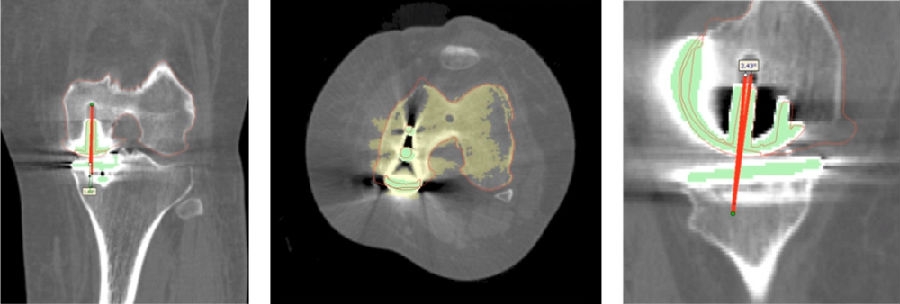

术前确认方案,包括大小型号,冠状矢状以及轴面上不同位置,如何选择每个人比较合适的假体相关位置。

术前确认方案

同时,笔者团队也在和导板公司进行合作,把用术后CT和术前CT进行匹配,来验证术前规划的偏离度有多少,包括胫骨后倾、冠状面内倾、轴面胫骨假体旋转、股骨在冠状面的角度、股骨在轴面上的旋转角度以及在矢状面上屈伸角度。

符合度验证

简单总结一下近期的数据,共20例患者的20例膝关节,男5人(25%),女15人(75%),左膝11例(55%),右膝9例(45%)。平均年龄69.8+5.6岁。以±3°作为整个导板设计规划与实际实施的幅度标准。术前规划与术后实际型号没有任何区别,是100%的符合度。

胫骨后倾角有95%的符合度,胫骨内翻角是100%的符合度;胫骨旋转仍然存在一个相对大的差距,但是比传统工具要更好,有70%的病人胫骨内旋角是在范围之内。

股骨在冠状面的角度上也是比较好的表现,股骨内翻角存在95%的符合度,股骨内外旋转角稍差一点,但也达到70%。目前唯一还存在不太满意的地方就是矢状面上股骨假体低头,这个角度偏差度和术前规划差距较大,有50%的准确。